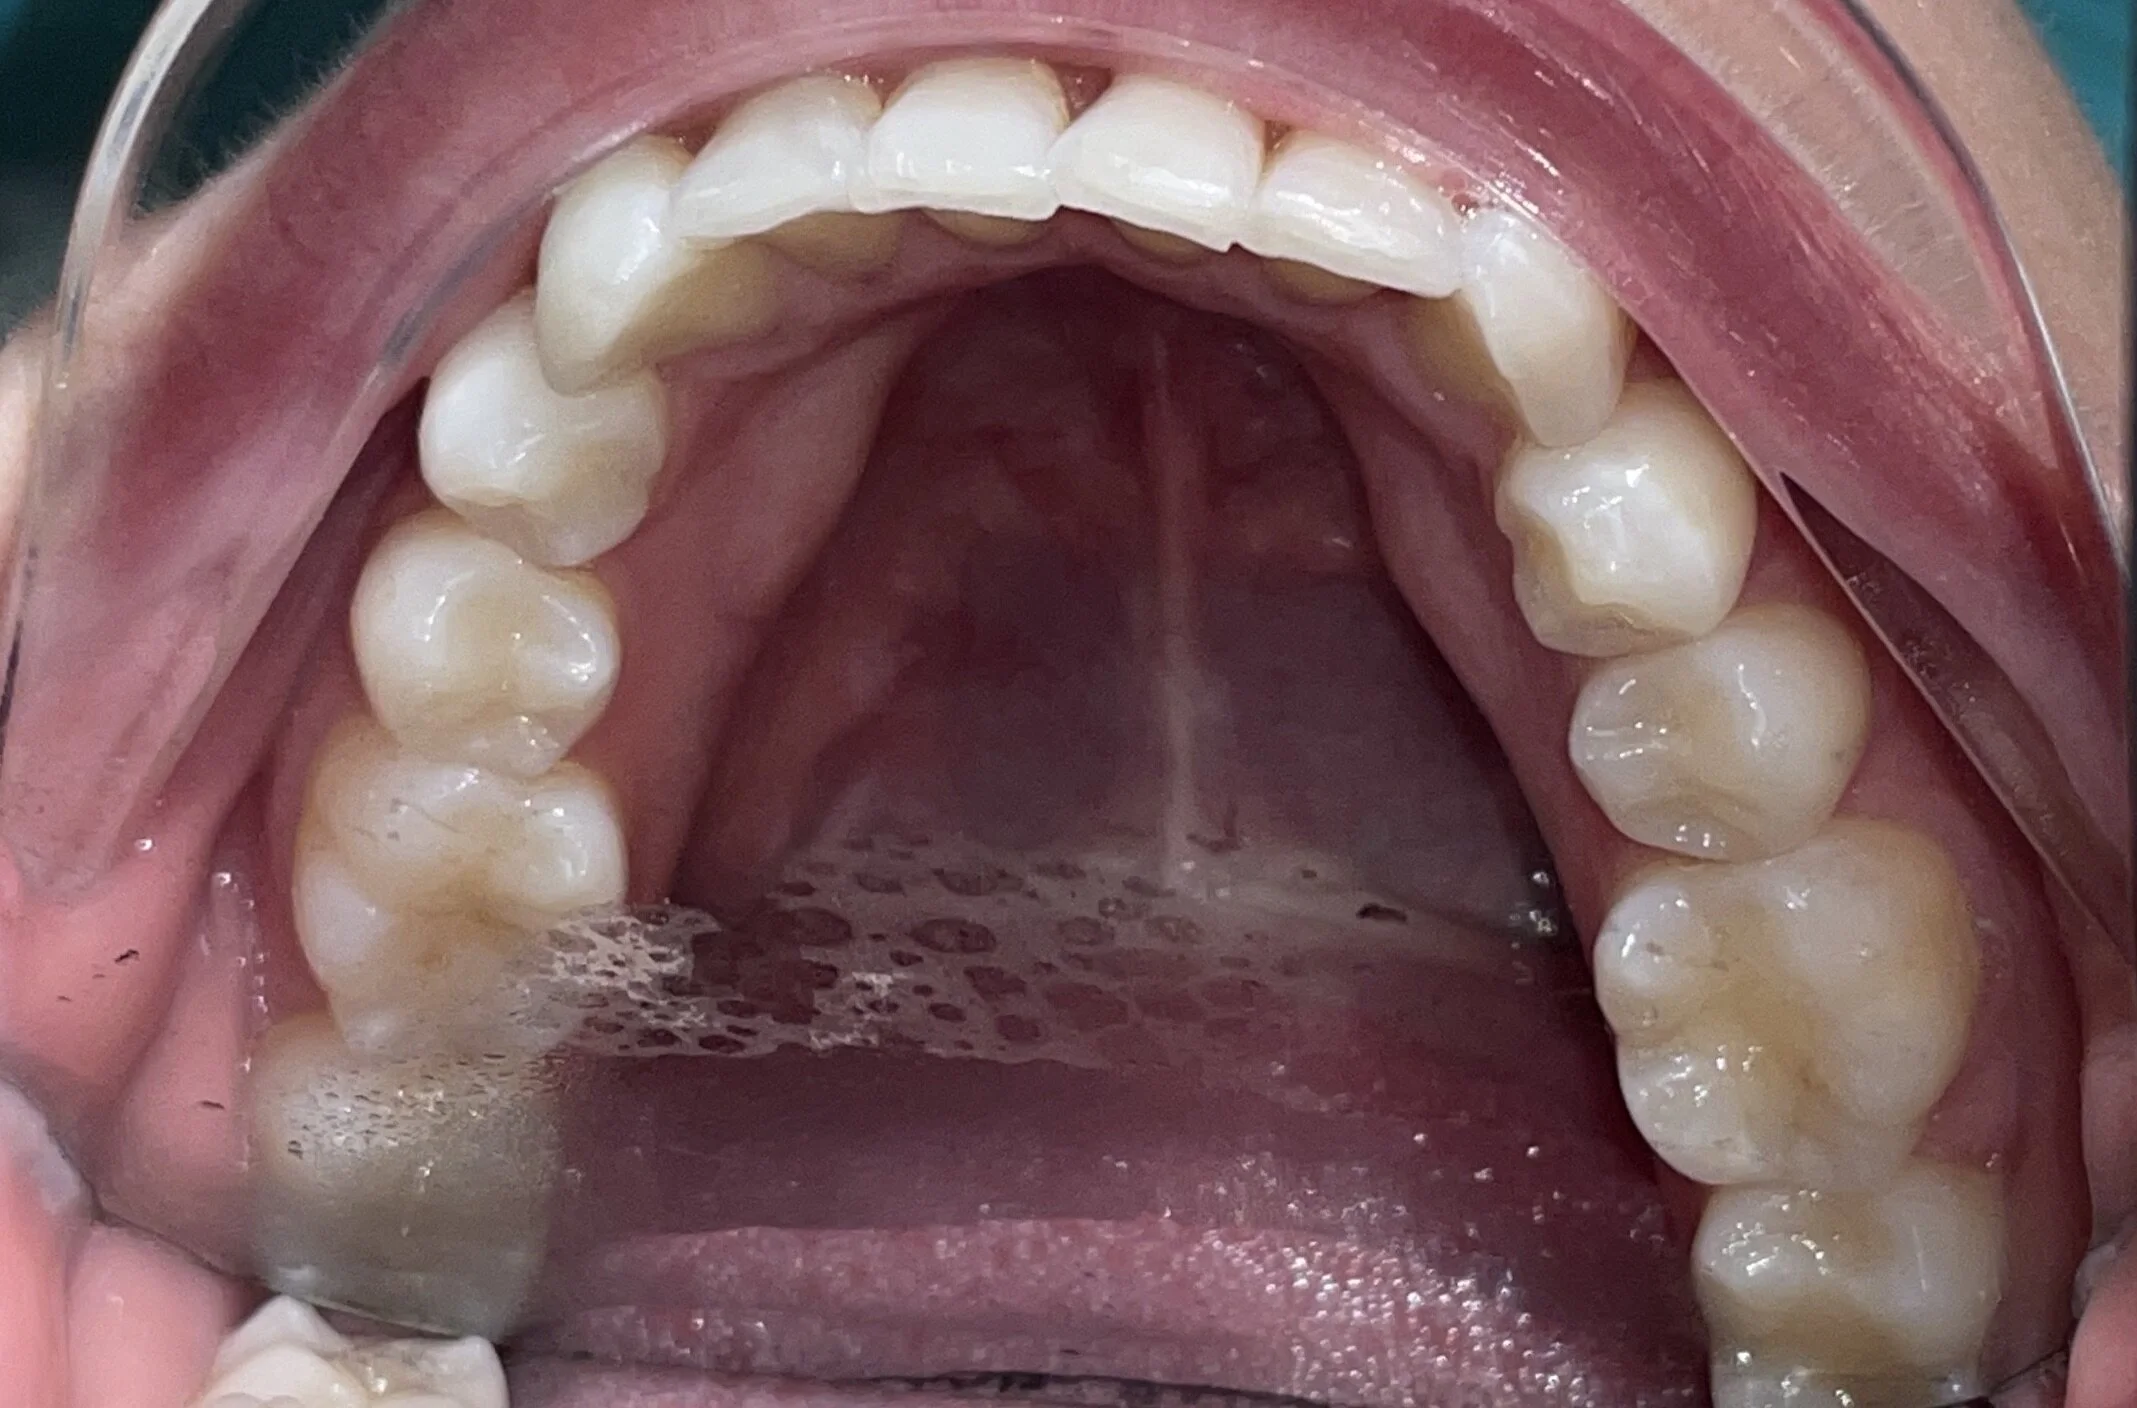

25 year Old Female

Examination:

• Comprehensive, FM/PANO., Perio Chartin, Dental Health Scan

Evaluation

• Crowding Due to Supernumerary 10A

• Midline Shift

Treatment:

• Invisalign Comprehensive Treatment with the extraction of 10A

• 2 ClinChecks:

• 1st ClinCheck : 29 aligners/ 14 day wear for the first three trays and 7 day wear until finish

• 2nd ClinCheck: 12 aligners/ 7-day wear

• (Refinement was needed because of COVID – Damn!!)

• Treatment time: 1 year

• Acceleration

• Munchie Madness Protocol: Pink and Blue 15min/4x day

• Case Finish

• Incisal manicuring

• Scanned for Viveras